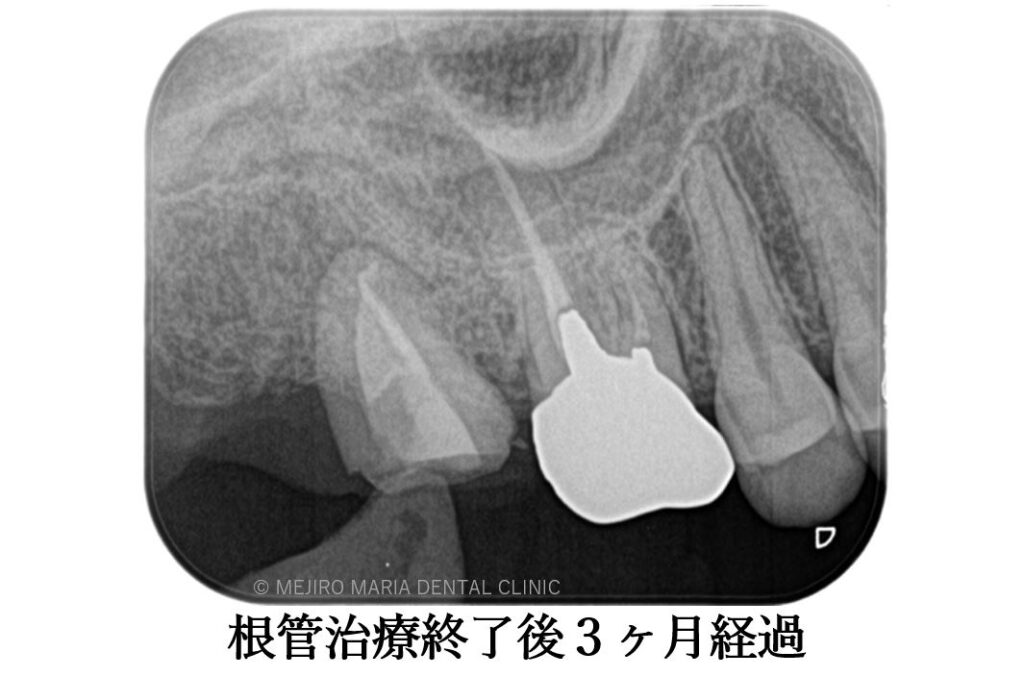

精密根管治療終了後3ヶ月で、術前に確認できた病変の縮小は顕著に確認でき、予後経過は良好と判断します。今後、最終補綴処置に移行し経過観察を行っていきます。

手術後、2週間で移植歯の生着を確認し、通法通りの精密根管治療を施したことで、根尖周囲組織に確認できた病変も3ヶ月後の経過観察では縮小を確認しました。